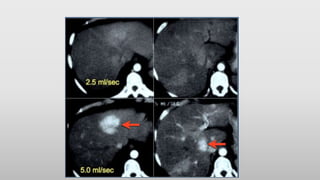

• On the left a patient who underwent

two phases of arterial imaging at 18

and 35 seconds. In the early arterial

phase we nicely see the arteries, but

we only see some irregular

enhancement within the liver.

• In the late arterial phase we can

clearly identify multiple tumor

masses.

• Notice that in the late arterial phase

there has to be some enhancement of

the portal vein.

• Timing of scanning is important, but

almost as important is speed of

contrast injection.

• For arterial phase imaging the best

results are

with an injection rate of 5ml/sec.

• There are two reasons for this better

enhancement: at 5ml/sec there will be

more contrast delivered to the liver

when you start scanning and this

contrast arrives in a higher

concentration.

• On the left a patient with cirrhosis

examined after contrast injection at

2.5ml/sec and at 5ml/sec.

• At 5ml/sec there is far better

contrast enhancement and better

tumor detection.

• Timing ofscanning is important, but almost as important is speed of contrast injection. • For arterial phase imaging the best results are with an injection rate of 5ml/sec. • There are two reasons for this better enhancement: at 5ml/sec there will be more contrast delivered to the liver when you start scanning and this contrast arrives in a higher concentration. • On the left a patient with cirrhosis examined after contrast injection at 2.5ml/sec and at 5ml/sec. • At 5ml/sec there is far better contrast enhancement and better tumor detection.

• #13 The upper images are of a patient with liver cirrhosis and multifocal hepatocellular carcinoma examined after contrast injection at 2.5ml/sec. Because of poor enhancement the examination was repeated at 5ml/sec. There is far better contrast enhancement and better tumor detection.